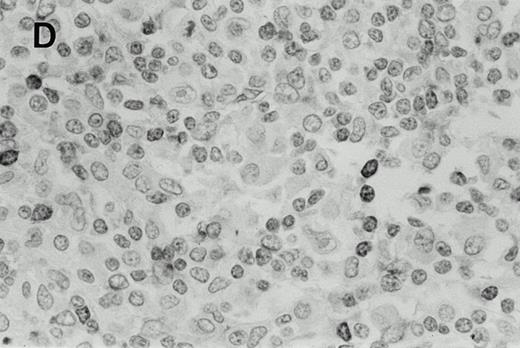

Immunohistochemistry of CD3 in case 1: (A) low (40×), (B) high (400×). CD3+ T cells are associated with clusters of H-RS cells, often forming a ring around the H-RS cells. Inset shows CD30+ H-RS cells. Immunohistochemistry of MB2 in case 2: (C) low (40×), (D) high (400×). MB2+ CLL cells are present around a nodule of HD. H-RS cells are admixed with T cells and histiocytes and only scattered MB2+ small lymphocytes are present.